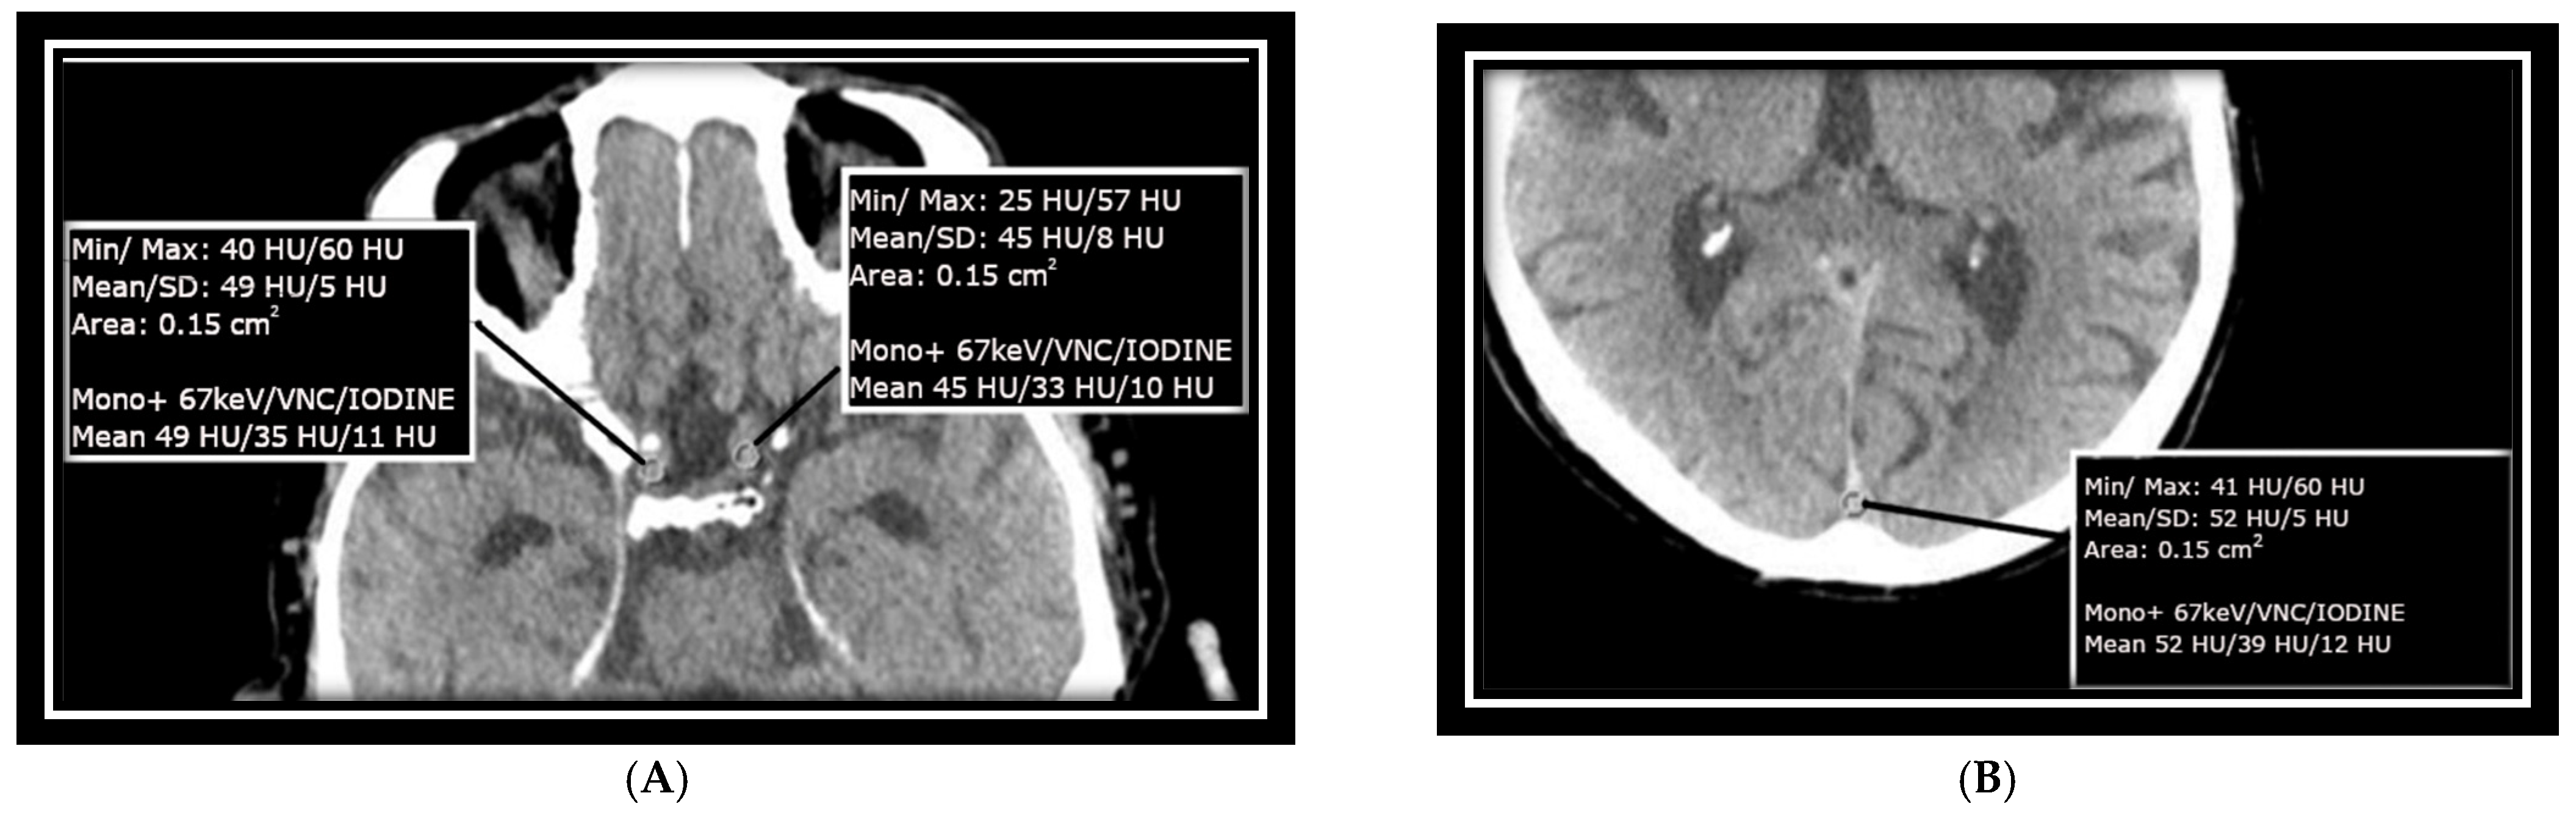

Measurements were taken at the confluence of sinuses (CS) over an area of approximately 15 mm2, as well as at the transitions between the left and right internal carotid arteries (ICAs) at the base of the skull in the intracranial part, each with an ROI of approximately 15 mm2. These areas were specifically selected to match the size of the ICA/MCA junction and to avoid calcified plaques that could impair measurement accuracy. The mean value of HU as well as SD measurements as baseline HU values were recorded from monoenergetic reconstructed data at +67 keV for each selected ROI, with a slice thickness of 1 mm and a soft kernel reconstruction. As shown in other studies and used in the clinical setting, this also is an energy with great discrimination between white and gray matter [17]. Virtual non-contrast (VNC) images and iodine images derived from the same slice of the scan were included as well. Image measurements were conducted using Siemens’ syngo.via software version 8.3 and are presented in Figure 1A,B.

Figure 1. Axial non-enhanced CT scans of the neurocranium, highlighting two key areas: (A) bilateral ICA (internal carotid arteries): measurements were taken to capture the dimensions and structural integrity of the internal carotid arteries on both sides. (B) Confluence of sinuses: focus was placed on this region to assess the venous confluence at the base of the skull. Each measurement was conducted with meticulous attention to detail, ensuring that the measurements strictly adhered to the anatomical boundaries of the vessels and avoided any measurement errors on the vessel walls.